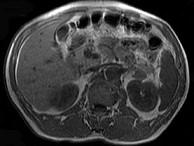

问题 男,52岁,下肢无力伴多饮多尿2年余,实验室检查:低血钾,血醛固酮水平及24小时尿醛固酮定量超过正常值,MRI检查如图所示,应诊断为()

选项 A.左肾上腺囊肿 B.左肾上腺腺瘤 C.左肾上腺嗜铬细胞瘤 D.左肾上腺髓脂瘤 E.左肾上腺转移瘤

答案 B